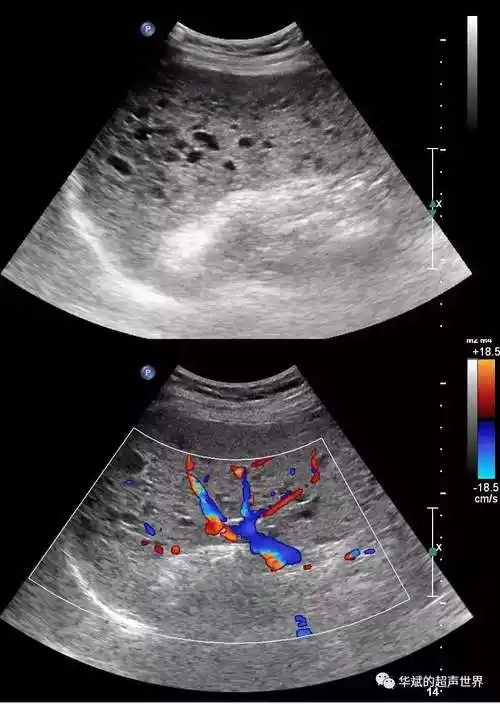

脾脏异常回声

超声解剖基础 | 脾脏_测量